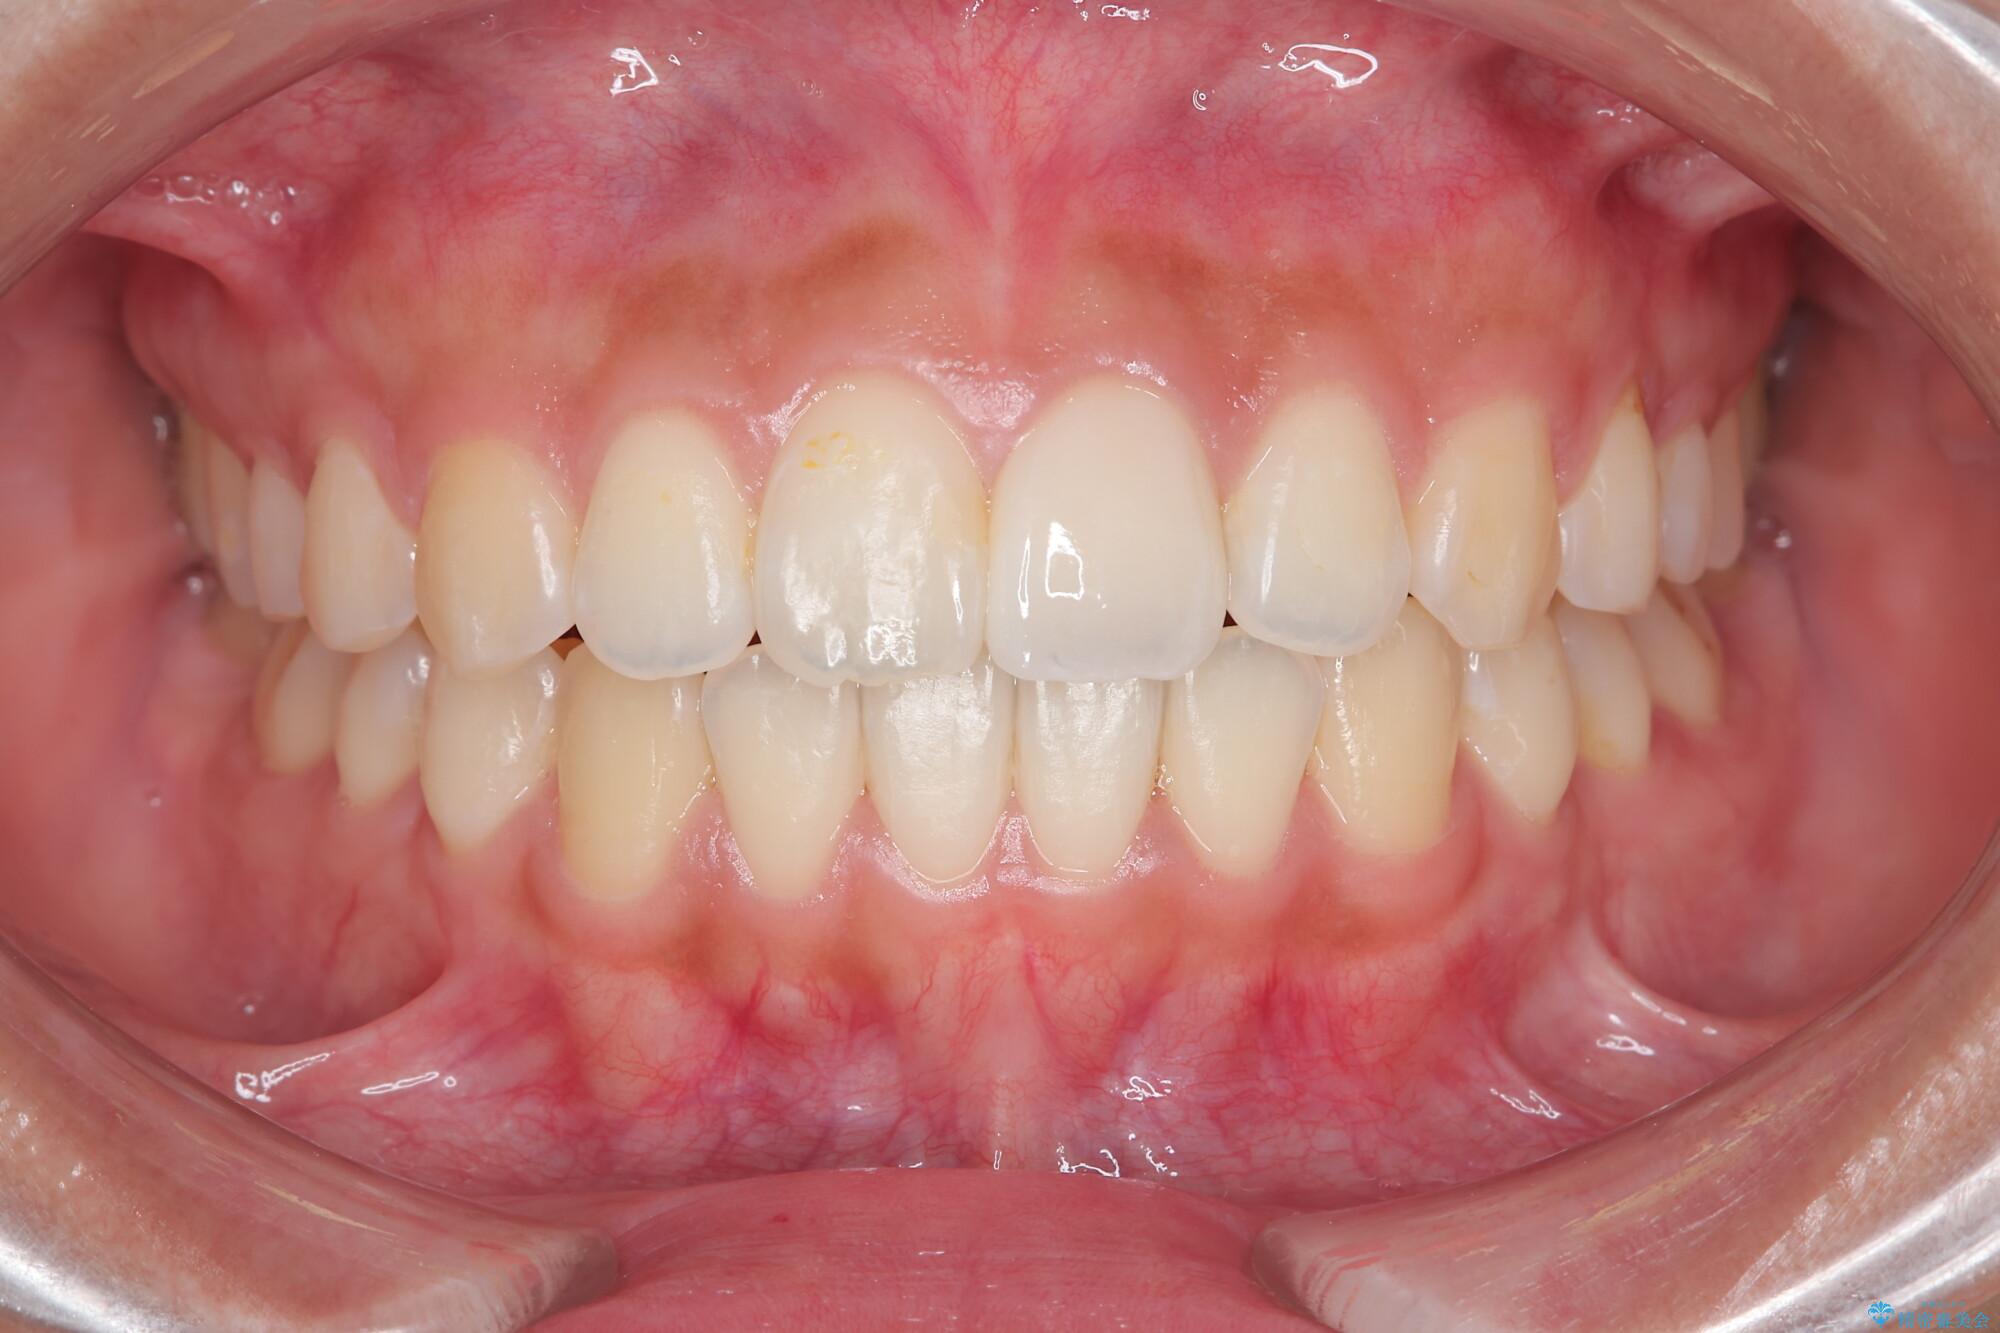

1年で歯並び、嚙み合わせともにしっかりと改善されました。

患者様にも、非常に噛みやすくなったと喜んでいただくことができました。